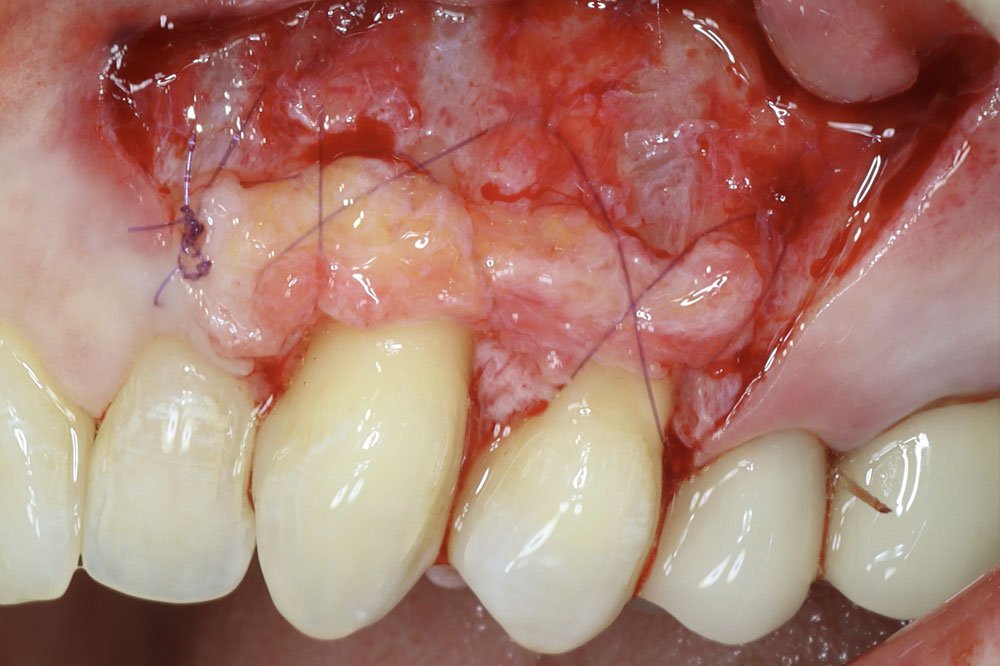

Periodontal Grafting and Crown Lengthening Surgery

- Connective tissue grafting techniques and guiltiness

- Develop Proficiency in Connective Tissue Grafting (CTG) Techniques

- Gain expertise in performing connective tissue grafts for soft tissue augmentation and root coverage.

- Understand how to choose the appropriate grafting technique based on patient needs and clinical scenarios to optimize results.

- Refine Advanced Suturing Techniques for Optimal Surgical Outcomes

- Master advanced suturing techniques that promote better healing, tissue stability, and cosmetic outcomes.

- Learn how to select and apply various suturing methods, such as interrupted, mattress, and continuous sutures, for different types of periodontal surgeries.

- Engage in hands-on practice sessions to enhance your technical skills in performing soft tissue grafting and crown lengthening procedures.

- Work with real tissue models or live patient demonstrations to refine your surgical techniques, graft placement, and suturing skills under expert guidance.

- Learn from Live Demonstrations of Advanced Procedures

- Observe live demonstrations of advanced periodontal procedures, including free gingival grafting, connective tissue grafting, and crown lengthening, to see these techniques in action.